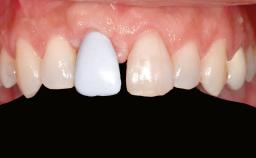

A 47-year-old Caucasian woman with a single-tooth edentulous space at the site of the left maxillary canine was referred for treatment. She had undergone traumatic extraction of this impacted canine several months before referral. Her chief complaint was the dissatisfying appearance of her smile. The patient desired a stable and esthetic rehabilitation of the site. Her dental history showed no evidence of periodontal disease or bruxism. She had no systemic diseases, was not taking any medications, and did not smoke. The extraoral examination revealed a high lip line and an inadequate soft-tissue volume at the defective canine site. Large black triangles were visible between the canine and its adjacent teeth.

Lip Line No exposure of papillae Exposure of papillae Full exposure of mucosa margin

Soft Tissue Anatomy Intact Defective